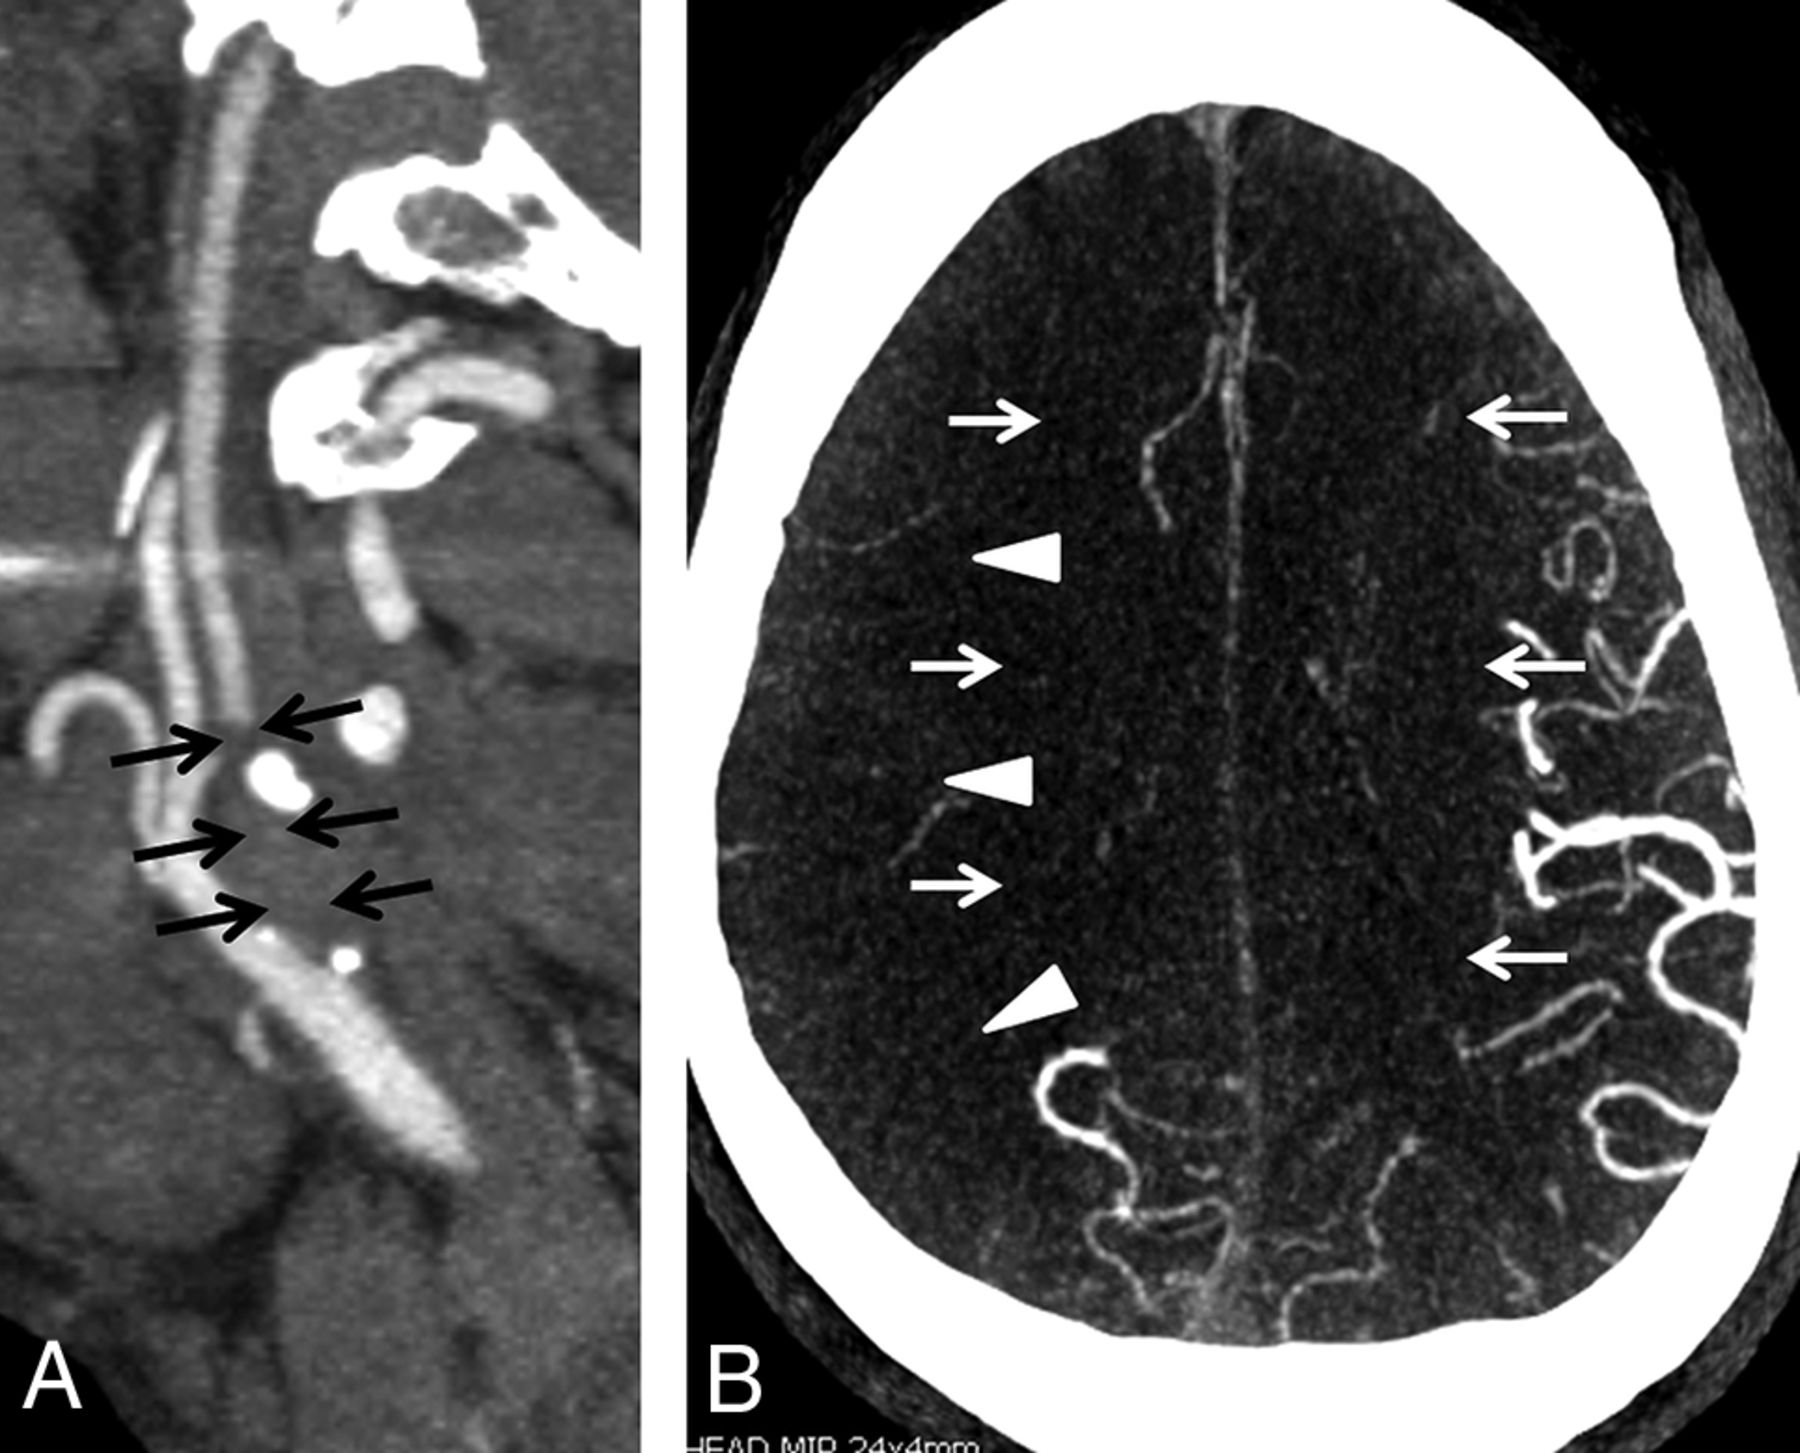

A, NCCT on the day of admission demonstrates subtle findings of acute ischemia in the right MCA (arrowheads) and bilateral ACA (arrows) territories, including hypoattenuation and loss of gray-white differentiation. B, Repeat NCCT on hospital day 2 demonstrates progression of acute infarcts in the right MCA and bilateral ACA territories, including worsening edema and mass effect.

Approximately 5 hours after hospital admission, NCCT revealed large areas of mild hypoattenuation and loss of gray-white differentiation in the territories of the right MCA and bilateral anterior cerebral arteries (ACAs) (Fig 1). Extracranial/intracranial CTA revealed a 20-mm segmental high-grade stenosis of the proximal ICA at the level of the ICA bifurcation (Fig 2). Given that the patient had evidence of mild, diffuse extracranial and intracranial atherosclerotic disease, the high-grade stenosis of the right ICA was favored to represent atherosclerotic disease; however, acute thrombus could have had a similar appearance. The intracranial CTA revealed no large-vessel occlusion, but there was markedly diminished flow in the distal branches of the right MCA and the bilateral ACAs (Fig 2). Approximately 24 hours later, a repeat NCCT revealed worsening cerebral edema and mass effect of the infarcts of the right MCA and bilateral ACA territories, consistent with the expected evolution of acute ischemia (Fig 1).